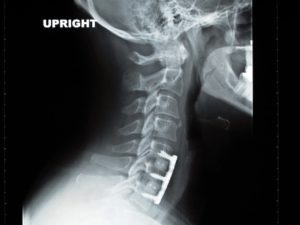

由於跌倒時壓碎了頸椎幾處的椎間盤, 導致我左右手臂跟雙手出現非常嚴重的麻痛與刺痛. 醫生緊急替我做了ACDF 頸椎前路椎間盤切除及椎體融合手術, 把摔碎的椎間盤取出, 放入人工椎間盤再以鈦合金的金屬片固定好 , 差不多就像上面從AllSpine Surgery Center借用的圖例一樣, 只是我受傷的頸椎位置不同. 所以基本上會需要施行ACDF手術的理由, 除了跟我的情形相同, 也有的人是頸椎有椎間盤突出, 嚴重的話可能也會藉由這個手術來改善出現的頸椎病症狀. 以下為摘自Asia Medical Specialists 對ACDF 手術的簡單介紹. Due to the impact of the fall, several intervertebral discs in my cervical spine were crushed, causing severe numbness and tingling in both my left and right arms. The doctor urgently performed an Anterior Cervical Discectomy and Fusion (ACDF) surgery for me. This involved the removal of the shattered intervertebral discs, replacing them with artificial discs, and securing them with titanium alloy metal plates and nails. The result of my procedure is similar to the illustration borrowed from the AllSpine Surgery Center above. The only difference is the location of my injured cervical spine. The reasons for undergoing ACDF surgery include situations similar to mine, where the intervertebral discs are crushed. Additionally, people with cervical disc protrusion may also opt for this surgery to alleviate severe cervical spine symptoms. The following is an excerpt from Asia Medical Specialists providing a brief introduction to ACDF surgery.

切除椎間盤後,在兩脊椎骨之間會有空隙,為防止脊椎骨塌下及互相摩擦,一般會利用移植骨或代替品填滿該位置。移植骨成為兩個脊椎骨之間的橋樑,以進行脊椎融合。移植骨和脊椎骨通常會以金屬板及骨釘固定在一起而不能調動。手術後身體會開始自然癒合,新的細胞也於移植骨周圍形成。三至六個月後,移植骨會與上下的脊椎骨融合成一塊堅實的骨頭 . 在儀器及融合術運作下,骨頭有機會沿著金屬板及骨釘生長 – 類似鋼筋混凝土般 .”After the removal of the intervertebral disc, there is a gap between the two vertebral bones. To prevent the collapse of the vertebral bones and friction between them, it is common to use transplanted bones or substitutes to fill this space. The transplanted bone serves as a bridge between the two vertebral bones, facilitating spinal fusion. The transplanted bone and vertebral bones are typically fixed together with metal plates and bone screws, making them immovable. Following the surgery, the body begins the natural healing process, and new cells form around the transplanted bone. Three to six months later, the transplanted bone solidifies into a firm structure, fused with the adjacent upper and lower vertebral bones. With the aid of instruments and fusion techniques, the bone has the opportunity to grow along the metal plates and bone screws, similar to the process of reinforcing concrete with steel.”